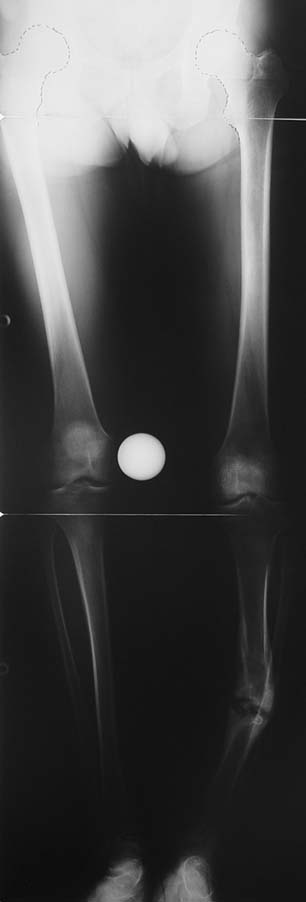

Uygun radikal debridman tüm nekrotik kemik ve yumuşak dokuların çıkartılmasını gerektirir, ve sıklıkla uzuvda instabiliteye neden olur. Kalan kemik ve yumuşak doku defektinin bir şekilde fiksasyonu ve rekonstrüksiyonu gereklidir. İlizarov’un ortaya koyduğu distraksiyon osteogenezi yöntemi, kaynamanın elde edilmesi, deformitenin düzeltilmesi, bacak boy eşitsizliğinin giderilmesi ve segmental defektlerin rekonstrükte edilmesi için başarıyla kullanılmaktadır.

Eksternal fiksatör ile geçen süre (eksternal fiksasyon indeksi), gereken distraksiyon miktarına bağlıdır ve bu süre boyunca bazı komplikasyonlarla karşılaşılabilir. Distraksiyon dönemi sona erdikten sonra, distraksiyon süresinin iki katını aşan konsolidasyon döneminde hastalar eksternal fiksatörü zorlukla tolere edebilirler. Yeterli konsolidasyon sağlanmadan eksternal fiksatör çıkartılırsa ise kırıklar, deformite ve kısalık oluşabilir. Hastanın fiksatör ile birlikte geçirdiği sürenin azaltılması ve böylece hasta konforunun ve aktivite düzeyinin arttırılması için intramedüller çivi üzerinden uzatma yöntemi uygulanmaktadır. Bu yöntemde distraksiyon dönemi sona erdiğinde kemiğin içindeki çivi statik olarak kilitlenmekte ve eksternal fiksatör çıkartılmaktadır. Stabilizasyon intramedüller çivi tarafından sağlandıktan sonra konsolidasyon dönemi gerçekleşmektedir. Bu şekilde hem eksternal fiksatörün uzun süre kalmasından hem de erken çıkartılmasından kaynaklanan komplikasyonların önüne geçilmektedir.